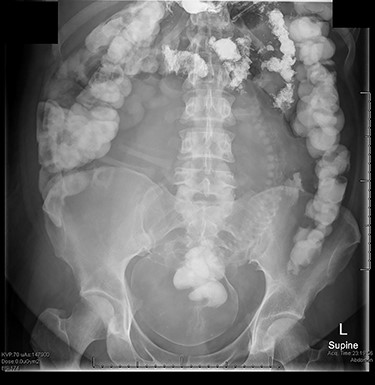

The case was discussed with the consultant on call. A magnetic resonance imaging (MRI) abdomen was performed, which was unremarkable. She was managed conservatively with an NG tube on free drainage; however, her symptoms persisted and she stopped passing flatus. She was counselled about radiation exposure, and the decision was made to trial Gastrografin oral contrast media followed by an abdominal X-ray (see Fig. 1). Her symptoms resolved, and she was discharged home. She later gave birth to a healthy baby girl at term.

Abdominal X-ray with Gastrografin oral contrast media seen in the large bowel, with her 30-week-old baby seen in the lower abdomen and pelvis.